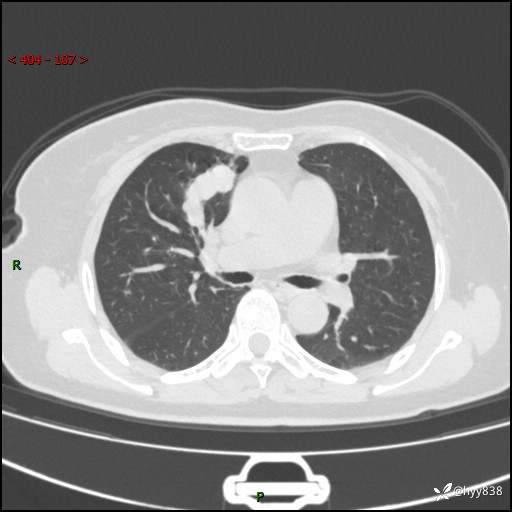

70岁/女,发现右上肺肿物10天。患者过敏体质,只有平扫,错过了一定可惜---结果公布~

【患者信息】:70岁/女

【主诉】:发现右上肺肿物10天

【现病史及既往史】:者10天前因“背部酸痛”于当地治疗,无发热,无呕吐,无头痛头晕等不适,胸部CT示右上肺肿物。遂来我科就诊,门诊看过病人后以“”收入我科, 自患病以来,精神、饮食、睡眠尚可,大小便正常,体力体重无明显减轻。

【检查】:胸部CT平扫(患者过敏体质,不能增强)